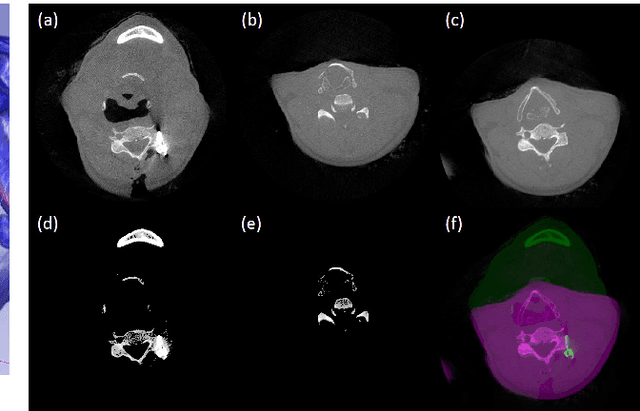

In computed tomography (CT), metal implants increase the inconsistencies between the measured data and the linear attenuation assumption made by analytic CT reconstruction algorithms. The inconsistencies give rise to dark and bright bands and streaks in the reconstructed image, collectively called metal artifacts. These artifacts make it difficult for radiologists to render correct diagnostic decisions. We describe a data-driven metal artifact reduction (MAR) algorithm for image-guided spine surgery that applies to scenarios in which a prior CT scan of the patient is available. We tested the proposed method with two clinical datasets that were both obtained during spine surgery. Using the proposed method, we were not only able to remove the dark and bright streaks caused by the implanted screws but we also recovered the anatomical structures hidden by these artifacts. This results in an improved capability of surgeons to confirm the correctness of the implanted pedicle screw placements.